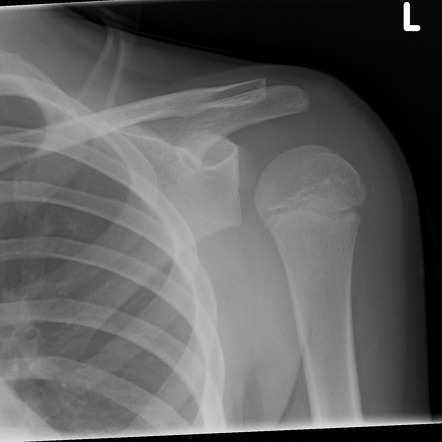

What investigation should be done for a shoulder dislocation?

Plain XR (AP + lat)

What will a AP view plain XR show in an ANTERIOR shoulder dislocation?

What will a AP view plain XR show in a POSTERIOR shoulder dislocation? (2 things)

What is a Lat view plain XR used for in a shoulder dislocation?

To differentiate between ANT + POST dislocations